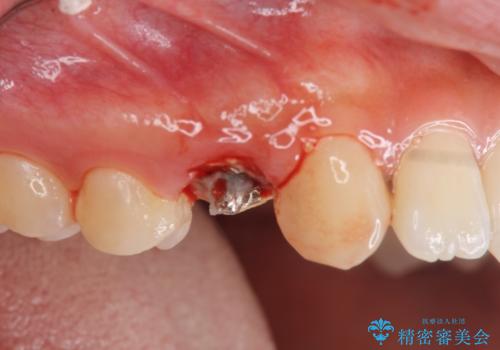

[銀歯の下の虫歯 ] 根管治療を伴う虫歯治療

![[銀歯の下の虫歯 ] 根管治療を伴う虫歯治療の症例 治療前](https://seimitsushinbi.jp/wp/wp-content/uploads/2020/05/89abd4c7a23874a1d4cee7f019e38bac-500x350.jpg?v=1590579075)